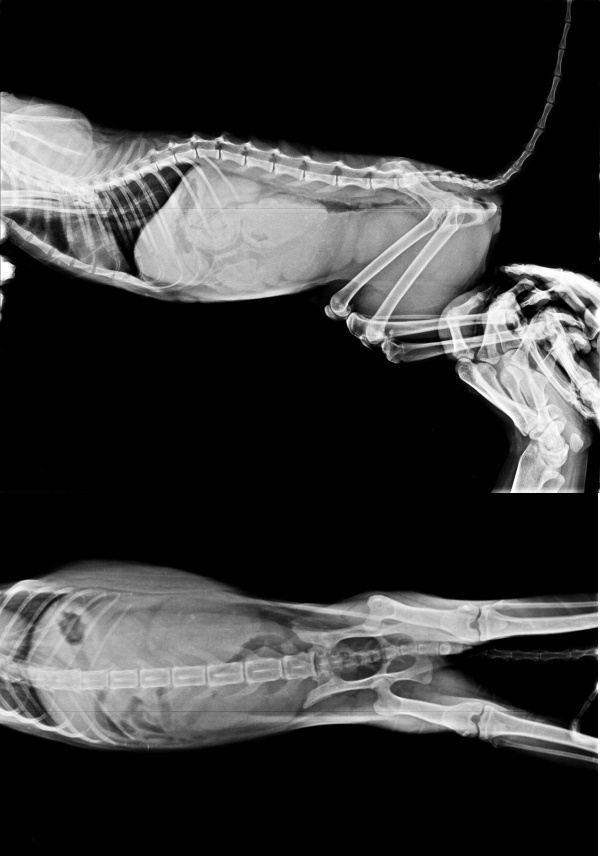

主題: 新莊收容所帶出鼻氣管炎的安安媽媽 申請者姓名: 臺北市支持流浪貓絕育計劃協會 花色: 申請日期: 2015-03-25 15:12:40 申請者部落格: 申請者臉書網址: 所在縣市/合作醫院: 台北市/極光動物醫院 治療費用: 7830元 需求人數: 9人 已結案 (2021-06-03 00:05:03) 報名人員: aky(已付款)、Kelvin Wu(已付款)、terranliu(已付款)、Annier(已付款)、Andreaws(已付款)、Ling(已付款)、Shan Shi Lai(已付款)、ERic YU(已付款)、Sunny Chen(已付款)、 候補人員: 動物病情說明: 協會於2015/3/11至新莊收容所帶出18隻喵喵,其中一隻體型十分瘦小母喵竟已懷孕,有感冒症狀不肯進食,因為身體贏弱無法麻醉進行手術,也擔心在體弱情況下無法抵抗病毒侵襲,陷於兩難,所幸血檢感染並不嚴重,x光檢查也沒有肺炎,無愛滋白血、也無貓瘟,先給與皮下輸液補充水分,早晚噴霧治療和給予促進食慾劑,在呼吸暢通後比較能聞到食物的味道,慢慢願意進食,住院五天後狀況穩定已帶回安養之家繼續噴霧治療,生命自有他堅韌之處,為母則強,醫師將貓咪取名安安,希望他能夠平安順利的生下小寶寶。安安住院醫療檢驗等等的費用還請各位幫忙。